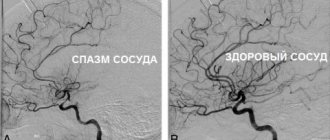

Биомеханизм развития заболевания точно не известен. Существует несколько теорий возникновения боли и сопутствующей симптоматики, наиболее популярной из которых является нейроваскулярная. Согласно этой точке зрения, мигрень начинается на фоне активации ядра тройничного нерва, которая вызывает сначала спазм, а потом расширение сосудов головного мозга. В результате ткани вокруг артерий становятся отечными, что и приводит к появлению болей. Кроме того, патологический процесс связан с нарушением обмена серотонина.

Некоторые ученые считают, что боль возникает исключительно на фоне резкого спазма и последующего расслабления сосудов, в результате чего происходит отек тканей (сосудистая теория). Однозначно доказано, что риск развития заболевания существенно выше у женщин, а также у людей, чьи родители или близкие родственники также страдали мигренью.

2. Аура. Возникает на фоне спазмов сосудов головного мозга. Чаще всего проявляется в виде зрительных нарушений (вспышки в виде пятен, зигзагов или молний перед глазами, искажение контуров предметов, выпадение отдельных полей зрении). Реже возникают вкусовые или слуховые расстройства, проблемы с координацией движений и т.п. Аура наблюдается не у всех пациентов.

Происходит это по причине резкого сужения главных артерий мозга и последующего дефицита притока к нему крови.